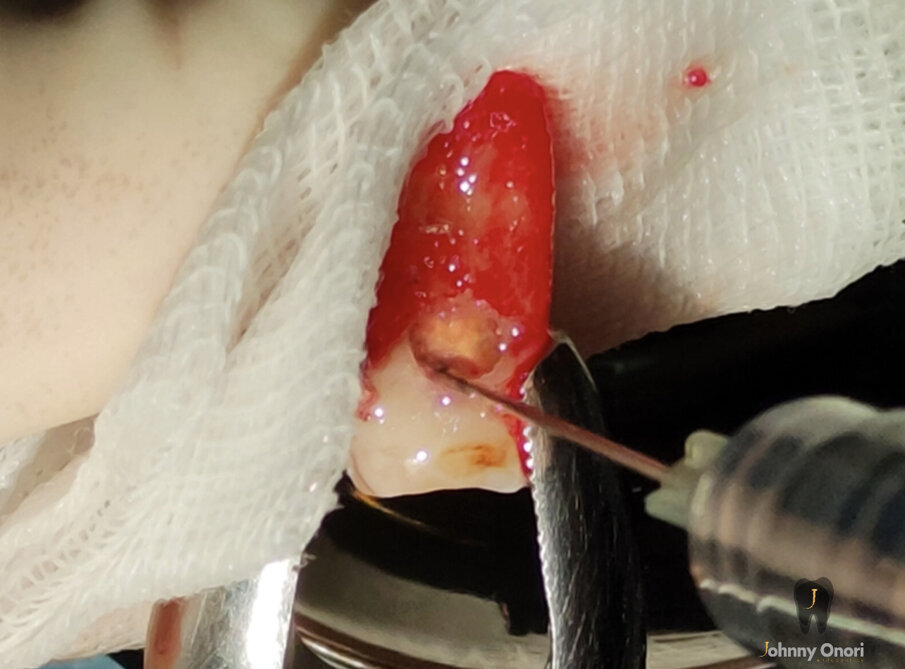

La CBCT è uno strumento utile in endodonzia, utilizzato per valutare l’entità del difetto di riassorbimento cervicale esterno, per rilevare e classificare la parodontite apicale e per valutare i riferimenti anatomici con maggiore precisione. Diversi autori hanno dimostrato che la CBCT è molto utile nella diagnosi di questo tipo di riassorbimento2-4. Nel caso clinico presentato, sono state osservate una lesione apicale e un ECIR, e la CBCT è stata utilizzata per osservare la dimensione della lesione periapicale e la dimensione e la localizzazione del difetto di riassorbimento nei tre livelli spaziali. Diversi fattori intervengono nella guarigione della parodontite apicale dopo l’intervento chirurgico periapicale, come la profondità della retro-preparazione apicale, che deve essere di almeno 3 mm, il materiale scelto per la retro-otturazione e il tempo di follow-up. Ulteriori scansioni CBCT sono state necessarie in questo caso per confermare la completa guarigione della lesione. L’estrusione chirurgica intenzionale è stata tentata con lo stesso trattamento chirurgico minimamente invasivo5, 6. Il tessuto di granulazione del difetto di riassorbimento è stato rimosso e l’area è stata sigillata con acido tricloroacetico al 90% e riempita con un cemento ionomero nano-ibrido di resina idrofila a doppia polimerizzazione (Geristore, DenMat; Figg. 4a, 4b). La chirurgia apicale è stata poi eseguita a 3 mm utilizzando le punte ultrasoniche del kit di chirurgia apicale EndoSuccess (ACTEON). La retro-otturazione è stata eseguita con un cemento minerale a triossido aggregato (CeraPutty, Meta Biomed), e il dente è stato riposizionato all’interno dell’alveolo, splittato con filo intrecciato semiflessibile per quattro settimane (Figg. 5a-5d)7, 8. Dopo sei mesi, è stata eseguita un’altra scansione CBCT per valutare la guarigione. Si è osservata una risoluzione quasi completa della lesione periapicale (Fig. 6). Anche la situazione intraorale sembrava buona, e non c’erano segni di patologia apicale sulla radiografia periapicale, che ha anche mostrato la guarigione quasi completa (Fig. 7). Il dente è rimasto asintomatico.

Figg. 4a, 4b - Estrusione chirurgica e sigillatura del riassorbimento. L’acido tricloracetico è stato applicato con un batuffolo di cotone per rimuovere tutto il tessuto riassorbitivo (a). Infine, la cavità è stata riempita con Geristore (DenMat) (b).

Figg. 4a, 4b - Estrusione chirurgica e sigillatura del riassorbimento. L’acido tricloracetico è stato applicato con un batuffolo di cotone per rimuovere tutto il tessuto riassorbitivo (a). Infine, la cavità è stata riempita con Geristore (DenMat) (b).